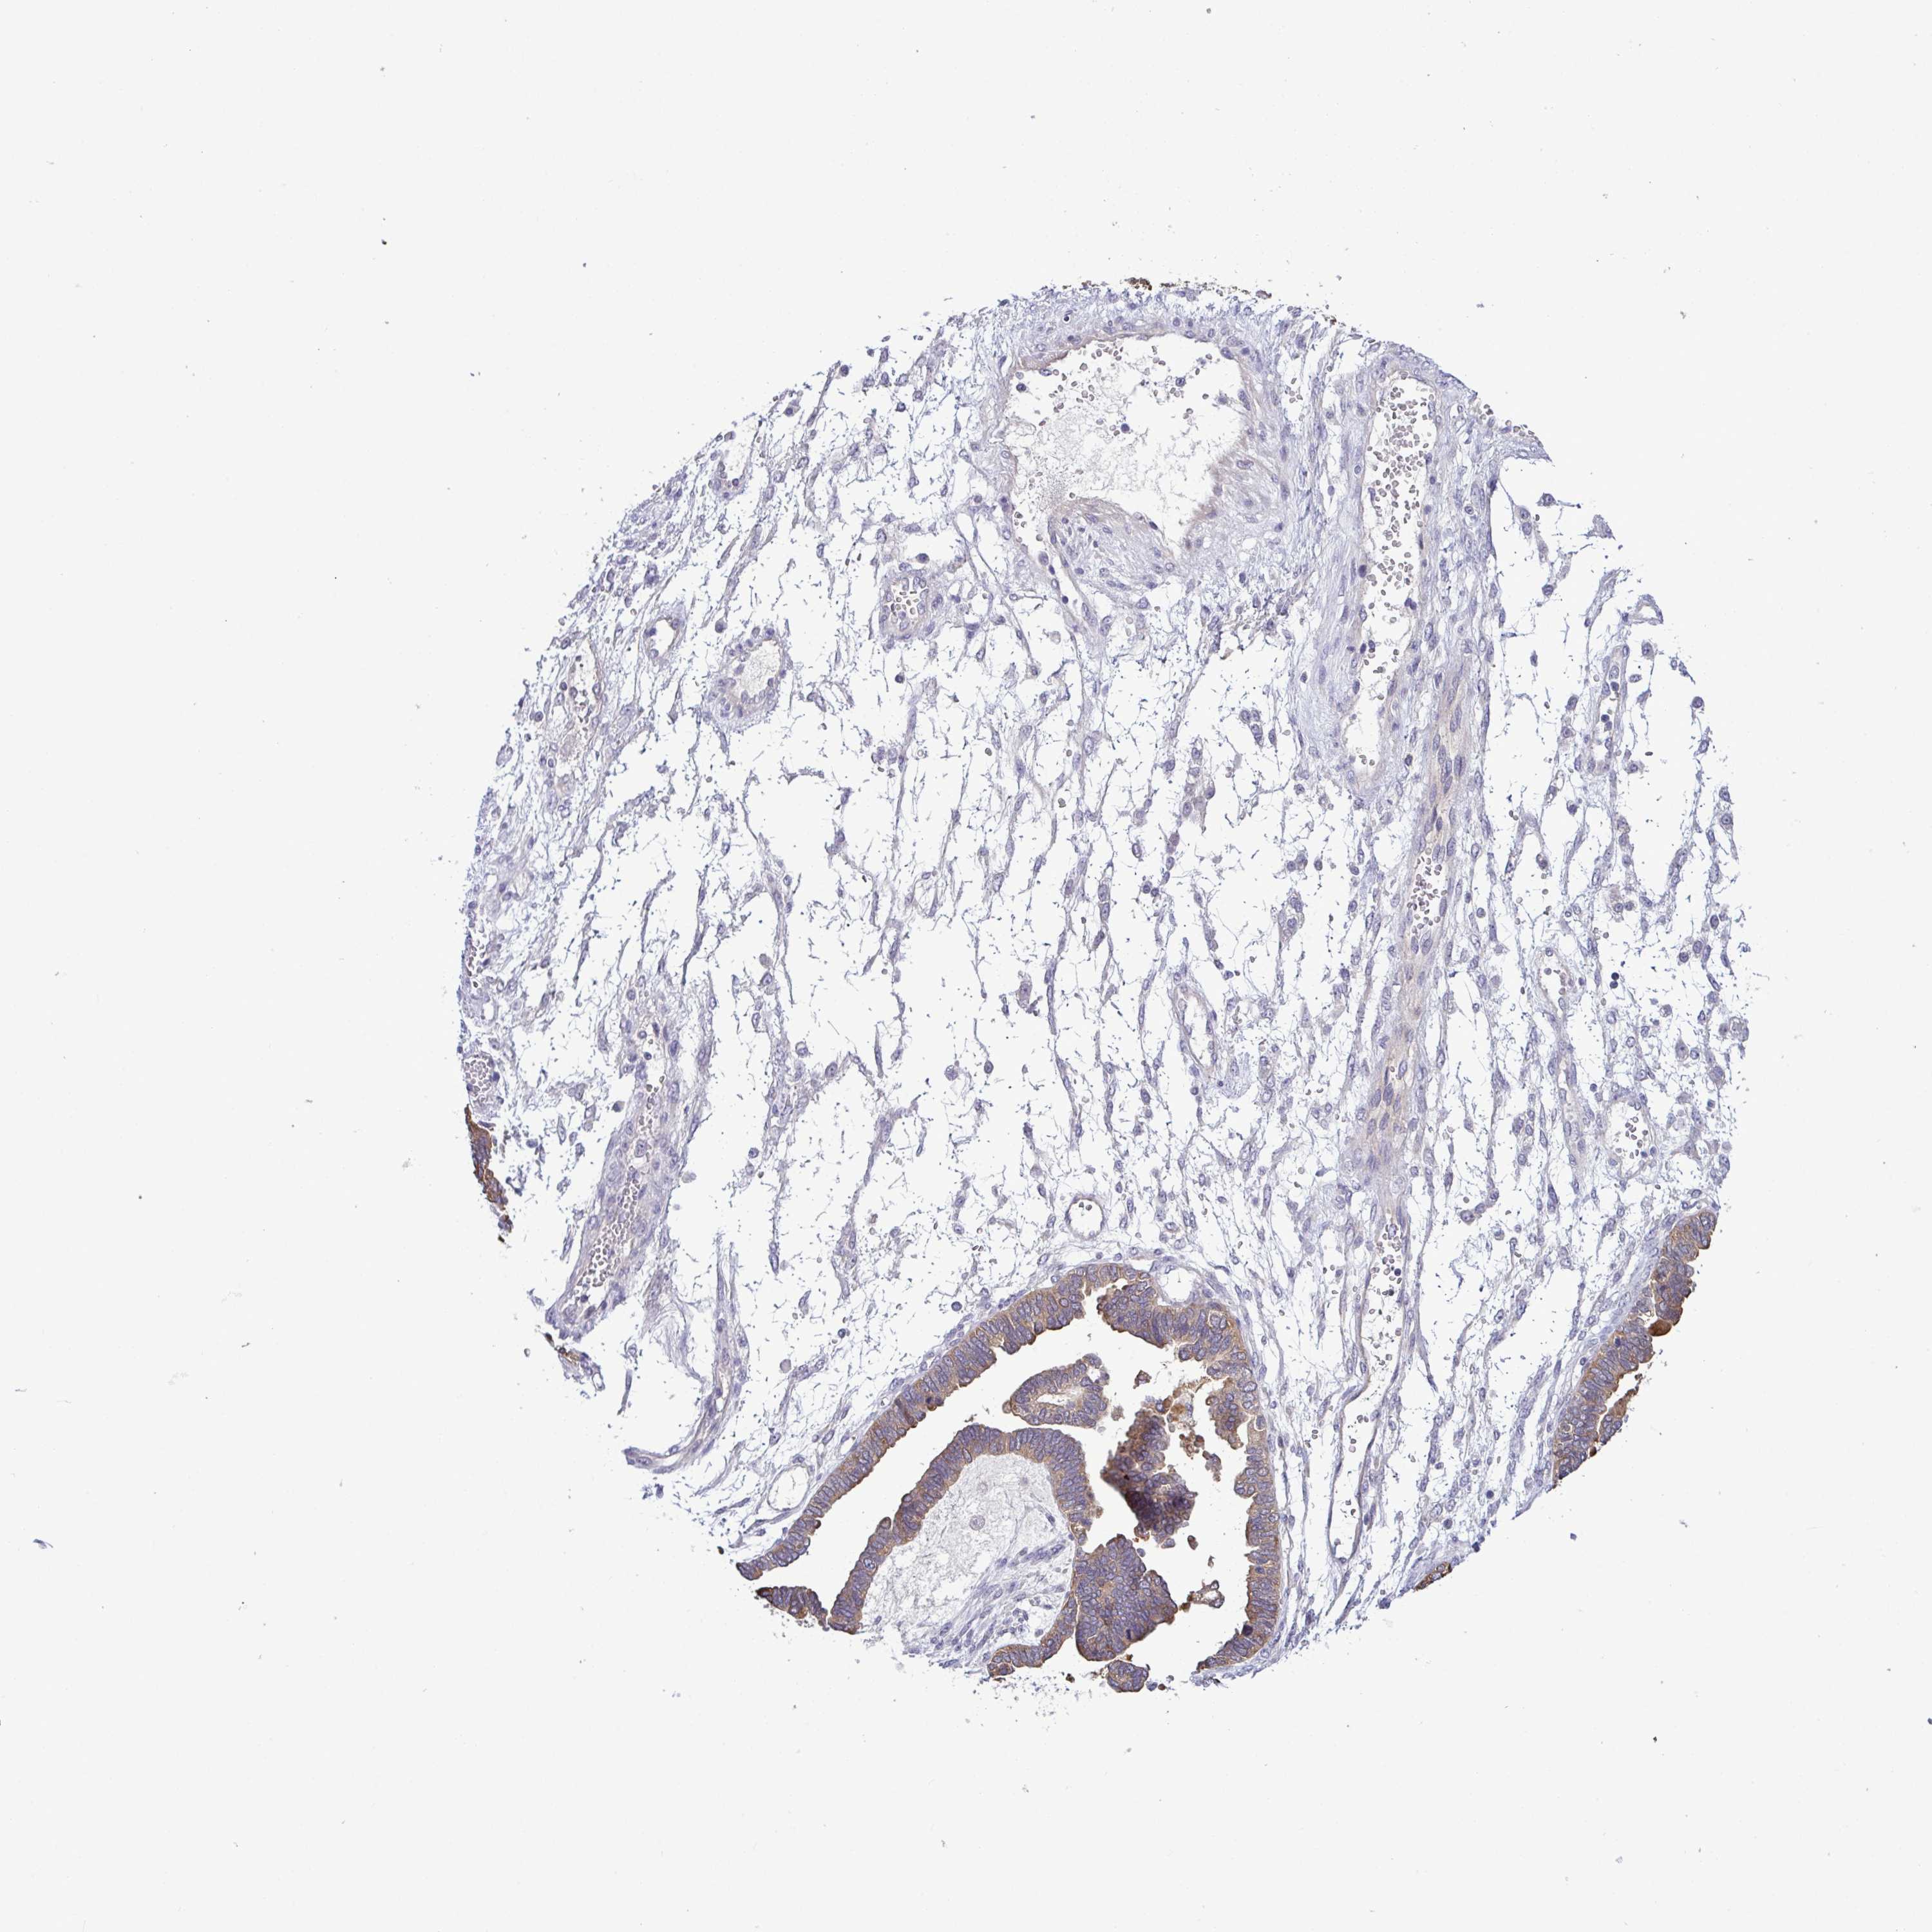

OVARIAN CANCER - Protein expressioni

A mouse-over function shows sample information and annotation data. Click on an image to view it in a full screen mode. Samples can be filtered based on level of antibody staining by selecting one or several of the following categories: high, medium, low and not detected. The assay and annotation is described here.

Note that samples used for immunohistochemistry by the Human Protein Atlas do not correspond to samples in the TCGA dataset.

Antibody stainingi

Antibody staining in the annotated cell types in the current human tissue is reported as not detected, low, medium, or high, based on conventional immunohistochemistry profiling in selected tissues. This score is based on the combination of the staining intensity and fraction of stained cells.

Each image is clickable and will lead to virtual microscopy that enables deeper exploration of all samples and also displays staining intensity scores, fraction scores and subcellular localization as well as patient and tissue information for each sample.

Antibody HPA055192

Antibody HPA057142

Cystadenocarcinoma, serous, NOS

Cystadenocarcinoma, mucinous, NOS

Carcinoma, endometroid